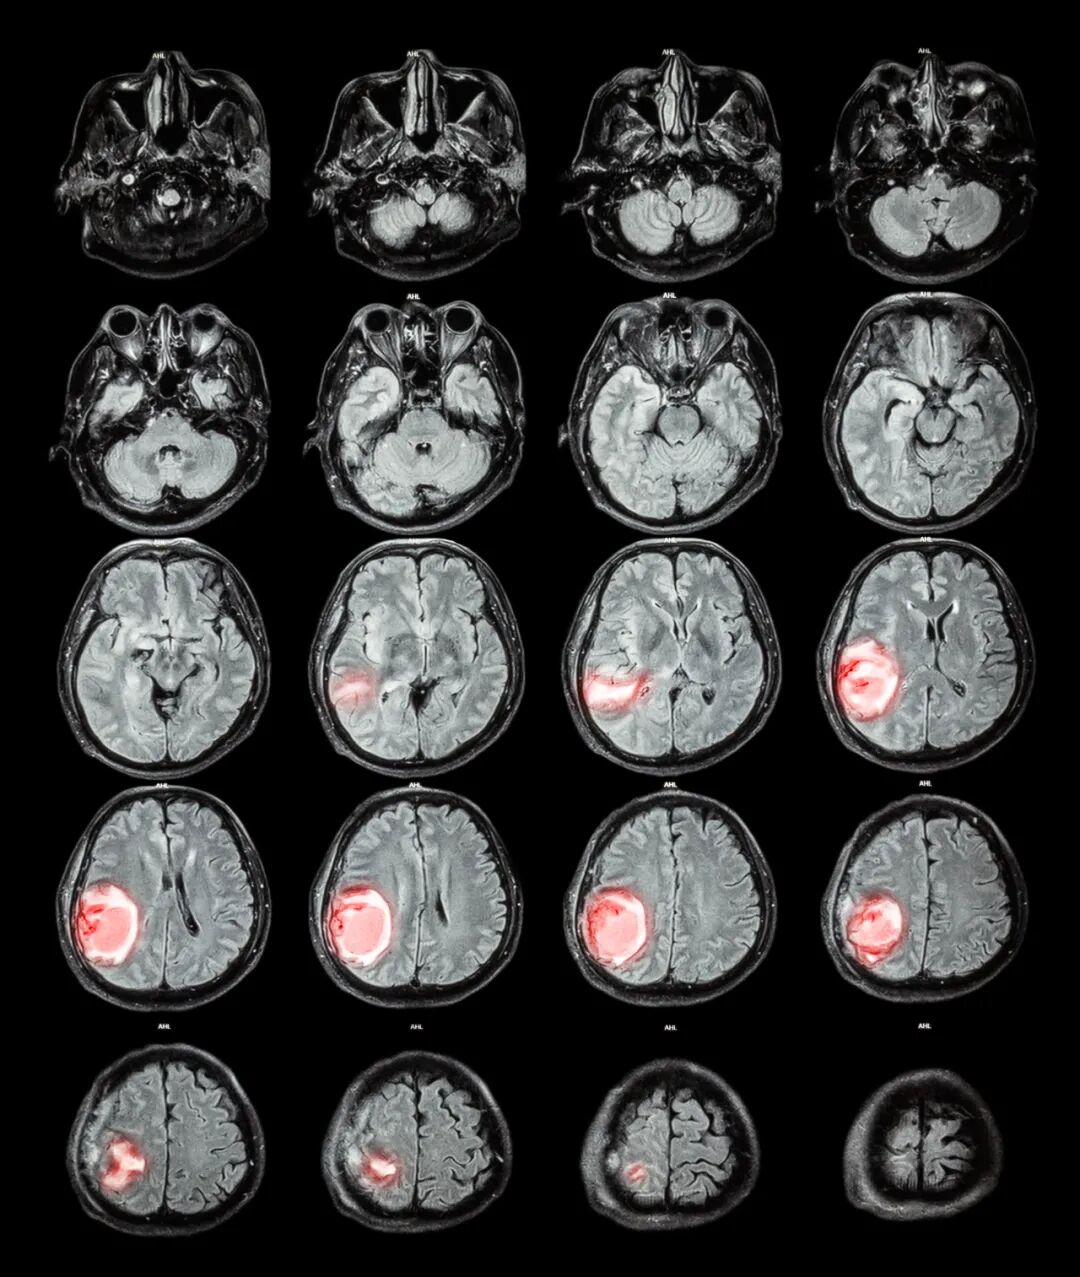

图源:参考文献【2】 原发性脑瘤:这些肿瘤起源于大脑或脊髓本身,而非其他部位的转移。例如: 胶质瘤:来源于支持神经细胞的胶质细胞,占所有脑瘤的50%以上。常见的胶质瘤类型包括: 星形细胞瘤:起源于星形胶质细胞,可分为低级别(如弥漫性星形细胞瘤)和高级别(如胶质母细胞瘤,GBM)。 少突胶质细胞瘤:来源于少突胶质细胞,通常生长缓慢,但也可以表现为高级别的恶性肿瘤。 室管膜瘤:源自大脑或脊髓的室管膜细胞,通常发生在儿童和青少年中。 髓母细胞瘤:一种起源于小脑的高恶性度脑瘤,多见于儿童,是最常见的儿童恶性脑瘤之一。 继发性(转移性)脑瘤:这种肿瘤是身体其他部位(如肺、乳腺或皮肤的黑色素瘤)癌症的转移,形成于大脑或脊髓内。这类脑瘤在成人中比原发性脑瘤更常见。 脑实质肿瘤:如胶质瘤,发生在大脑的功能性组织内。 脑膜肿瘤:如脑膜瘤,来源于覆盖大脑和脊髓的脑膜,通常为良性,但也可能导致严重的症状。 神经鞘瘤:如听神经瘤,起源于神经鞘,常见于听神经,通常为良性。 垂体腺瘤:发生在垂体腺,可影响激素的分泌,导致内分泌问题。 良性脑瘤:这些肿瘤通常生长缓慢,不会侵袭周围的正常组织,如脑膜瘤和大部分垂体腺瘤。 恶性脑瘤:这些肿瘤生长迅速,具有侵袭性,常常侵入周围的脑组织,并可能发生转移。胶质母细胞瘤是其中最具侵袭性的类型之一。 儿童脑瘤:儿童脑瘤与成人脑瘤在类型和发病率上有所不同,髓母细胞瘤和室管膜瘤在儿童中较为常见。 罕见脑瘤:一些罕见的脑瘤类型包括松果体区肿瘤、脊索瘤等。 图源:摄图网 脑瘤的转移方式主要依赖于肿瘤的性质、位置和生物学特性。与其他类型的癌症相比,原发性脑瘤较少发生转移。然而,某些类型的恶性脑瘤仍然有可能通过不同的途径扩散到身体的其他部位或脑内其他区域。 直接扩散:恶性脑瘤可以通过侵入相邻的脑组织来扩展。例如,胶质母细胞瘤(GBM)是高度侵袭性的脑瘤,常常通过直接扩散侵入周围的健康脑组织。 脑脊液传播:一些脑瘤,如髓母细胞瘤和室管膜瘤,可能通过脑脊液传播到脊髓或脑内其他区域。这种传播方式通常见于儿童脑瘤,导致肿瘤在中枢神经系统内的多处复发。 血行转移:尽管原发性脑瘤较少通过血液系统转移到身体的其他部位,但在少数情况下,如胶质母细胞瘤和其他高恶性度脑瘤,可能会转移到肺、骨骼或肝脏等器官。血行转移通常表明病情已经非常晚期,预后较差。 淋巴结转移:原发性脑瘤很少通过淋巴系统转移,因为大脑内的淋巴系统相对有限。但对于那些起源于头颈部的肿瘤,可能会扩散到邻近的淋巴结。 手术播种:在一些情况下,脑瘤手术或活检可能导致肿瘤细胞的种植性转移,特别是在操作过程中肿瘤细胞扩散到手术切口或脑脊液的路径上。不过,这种情况非常罕见。 图源:摄图网 并非所有脑瘤都是不可治愈的,国外论坛上一名网友提问,“切除脑瘤后还能和正常人一样生活吗?”,评论区有很多网友现身说法给予了他生活的信心。(论坛发言截取自Reddit) 译:我有可能得了脑瘤,我担心我是否能度过余生(我只有15岁)。有人能告诉我吗? 译:当然是!!我在19岁时切除了脑瘤,并获得了两个学士学位,目前是一名注册护士。我结婚了,养了两条狗,我参加过铁人三项,每年冬天都滑雪,我在伯利兹和鲨鱼一起潜水,现在我正计划去大峡谷旅行! 译:我在你这么大的时候,他们发现了我的第一个脑瘤。可能在那之前我一直带着它。他们观察了它四年,然后在它长大的时候把它取出来。又过了13年,我的第二个孩子才回来。即使现在有化疗和放疗,我的机会还是很大的。我记得当我十几岁的时候,他们第一次发现我的时候,我非常害怕。焦虑是正常的。但我们在肿瘤科学方面取得了长足的进步。我拿到了学位,帮助抚养侄子,生活得很好。我有个好朋友的妈妈在60多岁的时候,在30岁和50岁的时候切除了两个。她过着充实的生活。这是完全可能的。 译:这取决于你的肿瘤,你切除的效果,以及你选择的治疗方式。很多人的回答都是笼统的“会没事的”。这可能不是真的。我得了少突胶质细胞瘤,g2/3。接受了99%以上的切除,化疗杀死了剩余的细胞。切除后我有一些语言和记忆缺陷。他们康复了,可以全职工作了,还结交了新朋友,这是五年前的事了。我也保持着最亲密的关系。我很年轻:诊断时31/32。现在我快37岁了,可能是我一生中最好的时候。这在恢复中也起着作用。另外,在你被确诊为脑瘤之前不要被困难吓倒。 总体而言,尽管脑瘤的治疗和预后取决于许多因素,但医学的进步以及病友的支持为患者提供了更多的希望。随着医学研究的不断进展,未来将有更多创新的治疗方式,为脑瘤患者带来更多希望和可能性。如有需要帮助可直接联系小愈400-678-6998。